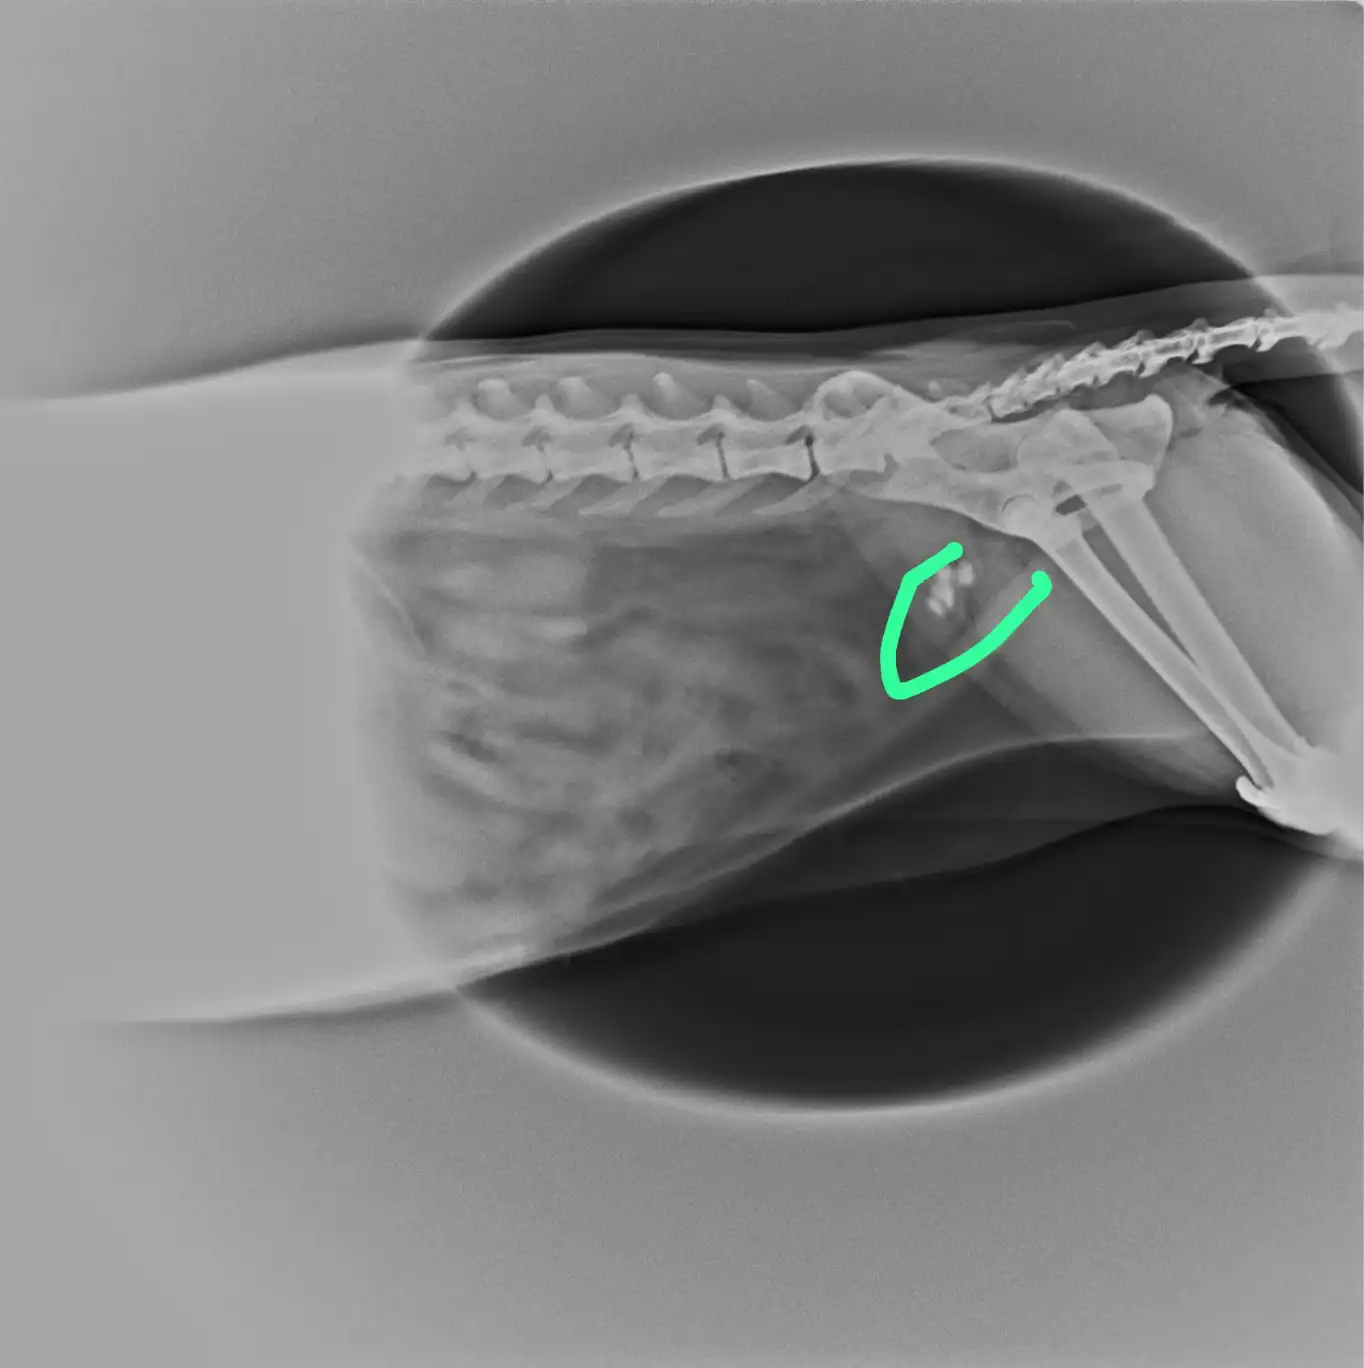

Veteriner röntgen; kemik yapılarını, eklemleri ve yumuşak dokuları görüntülememizi sağlayan, hızlı ve güvenilir bir radyolojik tanı yöntemidir. Kırıklar, eklem rahatsızlıkları, yutulan yabancı cisimler veya akciğer/kalp sorunları bu yöntemle tespit edilir.

• Travma Şüphesi: Düşme, çarpma veya trafik kazası sonrası oluşan kırık ve çıkıklar.

• Eklem Rahatsızlıkları: Topallama, hareket güçlüğü veya kalça displazisi belirtileri.

• Sindirim Problemleri: Kusma, şişkinlik veya yabancı cisim yutma şüphesi.